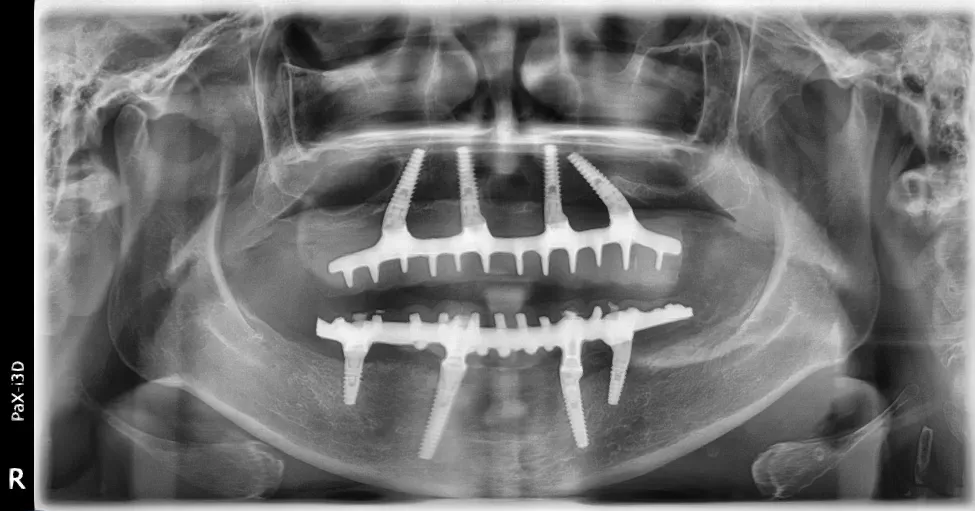

Le immagini radiografiche che seguono testimoniano alcune delle tante soluzioni tecniche che ho utilizzato per le arcate a carico immediato nel corso della mia carriera. Ogni caso presenta sfide diverse e richiede un approccio personalizzato.

Anche nei pazienti anziani con protesi mobili (dentiere) che presentano condizioni critiche dal punto di vista osseo, gli interventi di implantologia a carico immediato possono essere portati a termine con successo.

Tutto dipende dalle condizioni di salute generale e dall’anatomia residua. Non esiste un limite di età assoluto, ma solo una valutazione attenta del rapporto rischio-beneficio per ogni singolo paziente.